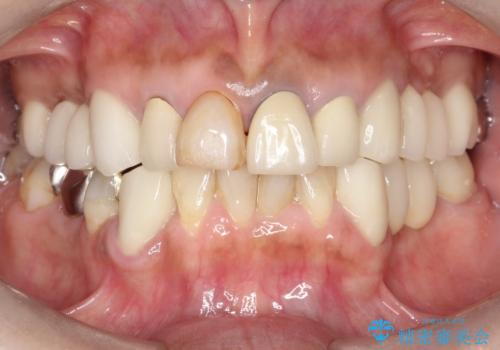

- 昔治療した前歯の色味が気になるとのことで来院されました。

昔に治療された前歯が変色しているのと、形態が自然ではありませんでした。

前歯2本をオールセラミックにすることにしました。